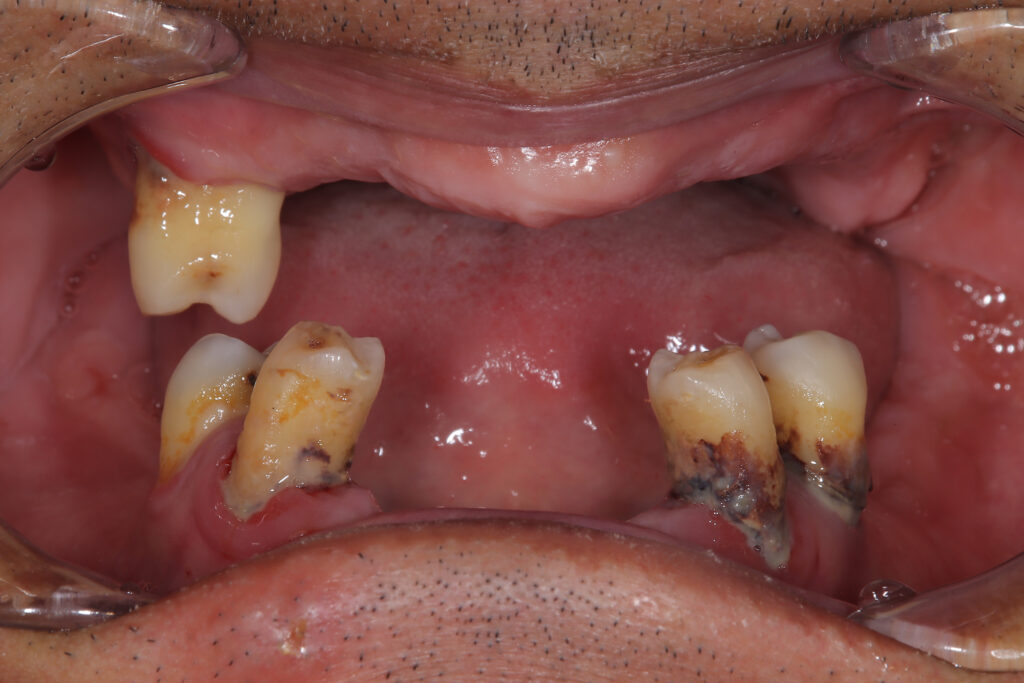

【上下オールオン4 インプラント】 50代 男性

【ご相談内容】 「しっかり噛めない。見た目も気になって人前で笑えない」とお悩みで来院されました。 【治療内容】 上下にオールオン4インプラント治療を行いました。少ない本数のインプラントで固定式の歯を作る方法で費用を抑えることができます。しっ